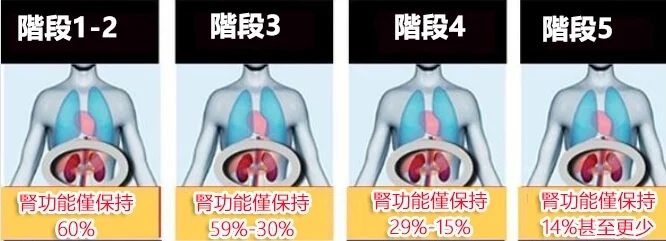

腎臟病最討厭的地方在於,它不痛不癢沒有明顯症狀,大部分人很難發現自己有腎臟病,等到發現就晚了!

患有腎病的患者們,基於大多數初期至中期CKD病患都不會有腎功能衰竭的症狀,

所以導致多數人往往在病情嚴重時,才發現自己患上腎病。

所以腎臟病的早期發現,早期治療,非常重要!